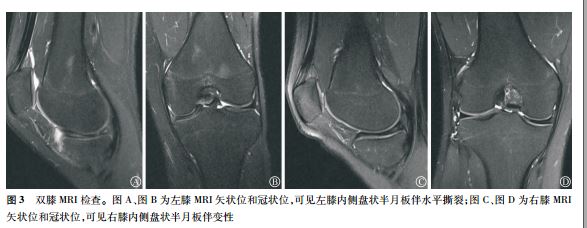

病例三 双膝内侧盘状半月板,仅一侧有症状。

患者男 性, 17 岁, 学生, 无特殊运动爱好史, 因“双膝不适感 10 余年, 左膝疼痛、 伸直受限 1 个月余”入院。 。 双膝 MRI 提示: 左膝内侧盘状半月 板撕裂伴前角 囊肿, 右膝内侧盘状半

月 板伴变性 。 因患者左膝疼痛及伸直受限,而右膝关节无明显症状, 不影响日 常生活及活动, 故

行左膝关节镜下内侧盘状半月 板成形术。